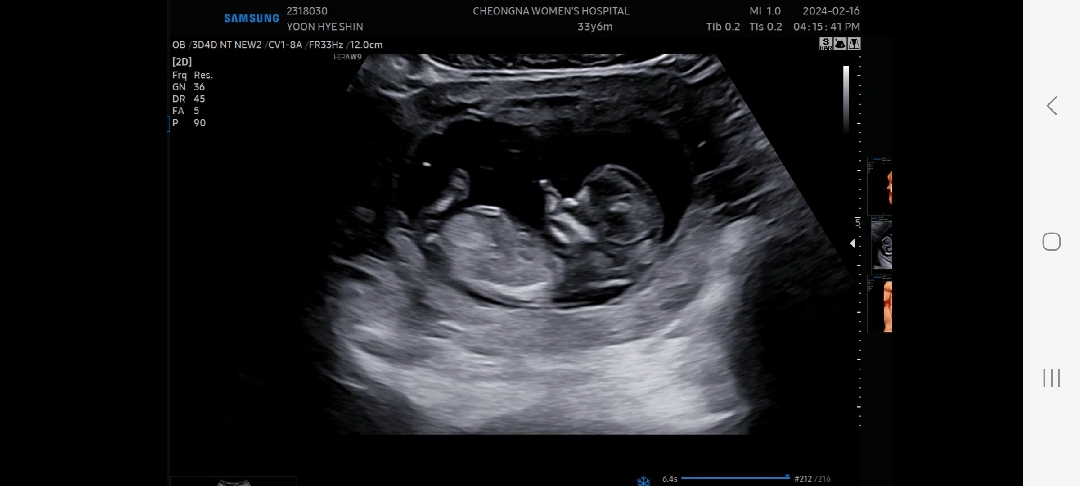

12주차 각도법 성별 확인 부탁드립니다 :)

각도법 확인부탁드립니다 :)